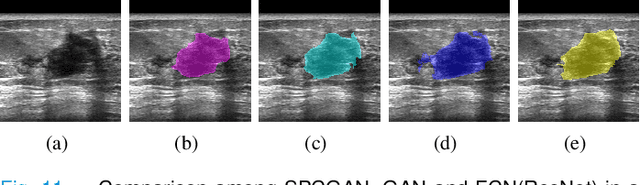

Abstract:Breast cancer is the most common invasive cancer with the highest cancer occurrence in females. Handheld ultrasound is one of the most efficient ways to identify and diagnose the breast cancer. The area and the shape information of a lesion is very helpful for clinicians to make diagnostic decisions. In this study we propose a new deep-learning scheme, semi-pixel-wise cycle generative adversarial net (SPCGAN) for segmenting the lesion in 2D ultrasound. The method takes the advantage of a fully connected convolutional neural network (FCN) and a generative adversarial net to segment a lesion by using prior knowledge. We compared the proposed method to a fully connected neural network and the level set segmentation method on a test dataset consisting of 32 malignant lesions and 109 benign lesions. Our proposed method achieved a Dice similarity coefficient (DSC) of 0.92 while FCN and the level set achieved 0.90 and 0.79 respectively. Particularly, for malignant lesions, our method increases the DSC (0.90) of the fully connected neural network to 0.93 significantly (p$<$0.001). The results show that our SPCGAN can obtain robust segmentation results and may be used to relieve the radiologists' burden for annotation.